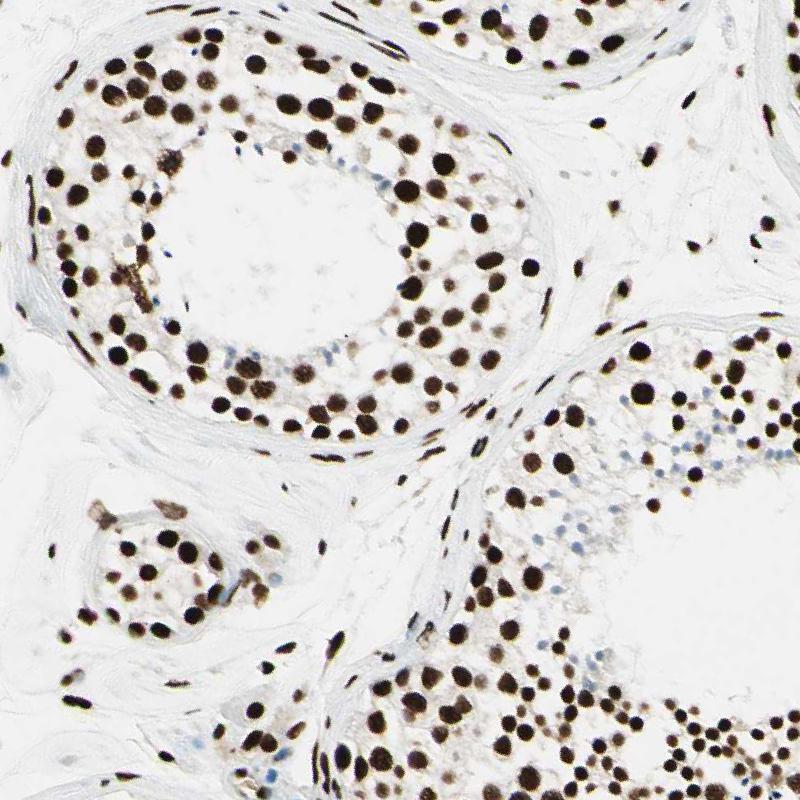

Immunohistochemistry analysis in human endometrium and liver tissues using HPA008784 antibody. Corresponding FUS RNA-seq data are presented for the same tissues.